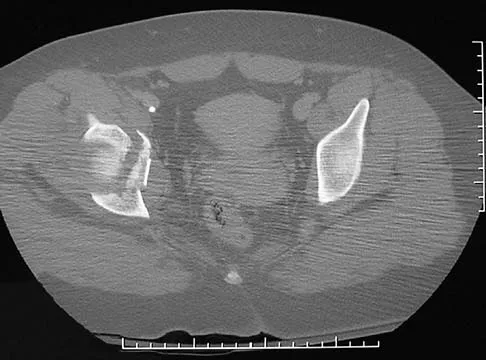

Figures 61a and 61b show the CT and MRI scans of a 40-year-old man who has hip pain. He undergoes total hip arthroplasty and curettage and cementation of the lesion as shown in Figure 61c. Histopathologic photomicrographs of the curettage specimen are shown in Figures 61d and 61e. What is the best course of treatment?

The definitive surgery would be removal of the entire resection bed, and in this case of dedifferentiated chondrosarcoma, a hemipelvectomy was performed. The MRI and CT scans show an aggressive cartilage lesion. The histology, representative of a dedifferentiated chondrosarcoma, shows a bimorphic low-grade cartilage lesion with high-grade spindle cell sarcoma. The cartilage lesion is usually an enchondroma or low-grade chondrosarcoma. The dedifferentiated portion is typically a malignant fibrous histocytoma, osteosarcoma, or fibrosarcoma. Weber KL, Pring ME, Sim FH: Treatment and outcome of recurrent pelvic chondrosarcoma. Clin Orthop Relat Res 2002;397:19-28.

- Pring ME, Weber KL, Unni KK, et al: Chondrosarcoma of the pelvis: A review of sixty-four cases. J Bone Joint Surg Am 2001;83:1630-1642